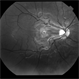

- fundus photograph, red-free, intraretinal microvascular abnormalities

- Intraretinal microvascular abnormalities